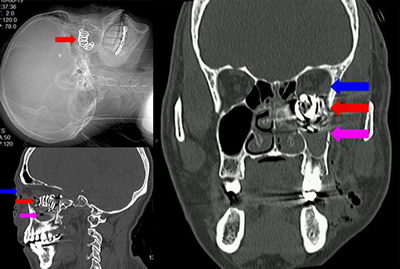

近日,我院耳鼻喉科急诊收住了一位因猎枪故障爆炸导致枪部件高速扎入面部的患者胡先生。入院时,其面部左眼眶、鼻窦处异物,眼睛红肿、流血、无法睁开,眼球不能转动,并伴有面部及鼻出血。接诊医师方秀玲为患者查体后发现其面部有一不规则创口、眼睑肿胀、左眼视力仅为30cm眼前指数。急查鼻窦及眼眶CT(图一A、B、C),CT显示左眼眶-鼻窦弹簧状高密度异物,诊断为合并眼球爆炸伤、多发角膜异物及视神经损伤。

图一 眼眶-鼻窦CT平扫示左眼眶-鼻窦高密度异物,红色箭头所示为弹簧状异物,蓝色箭头所示为眼眶,紫色箭头所示为上颌窦